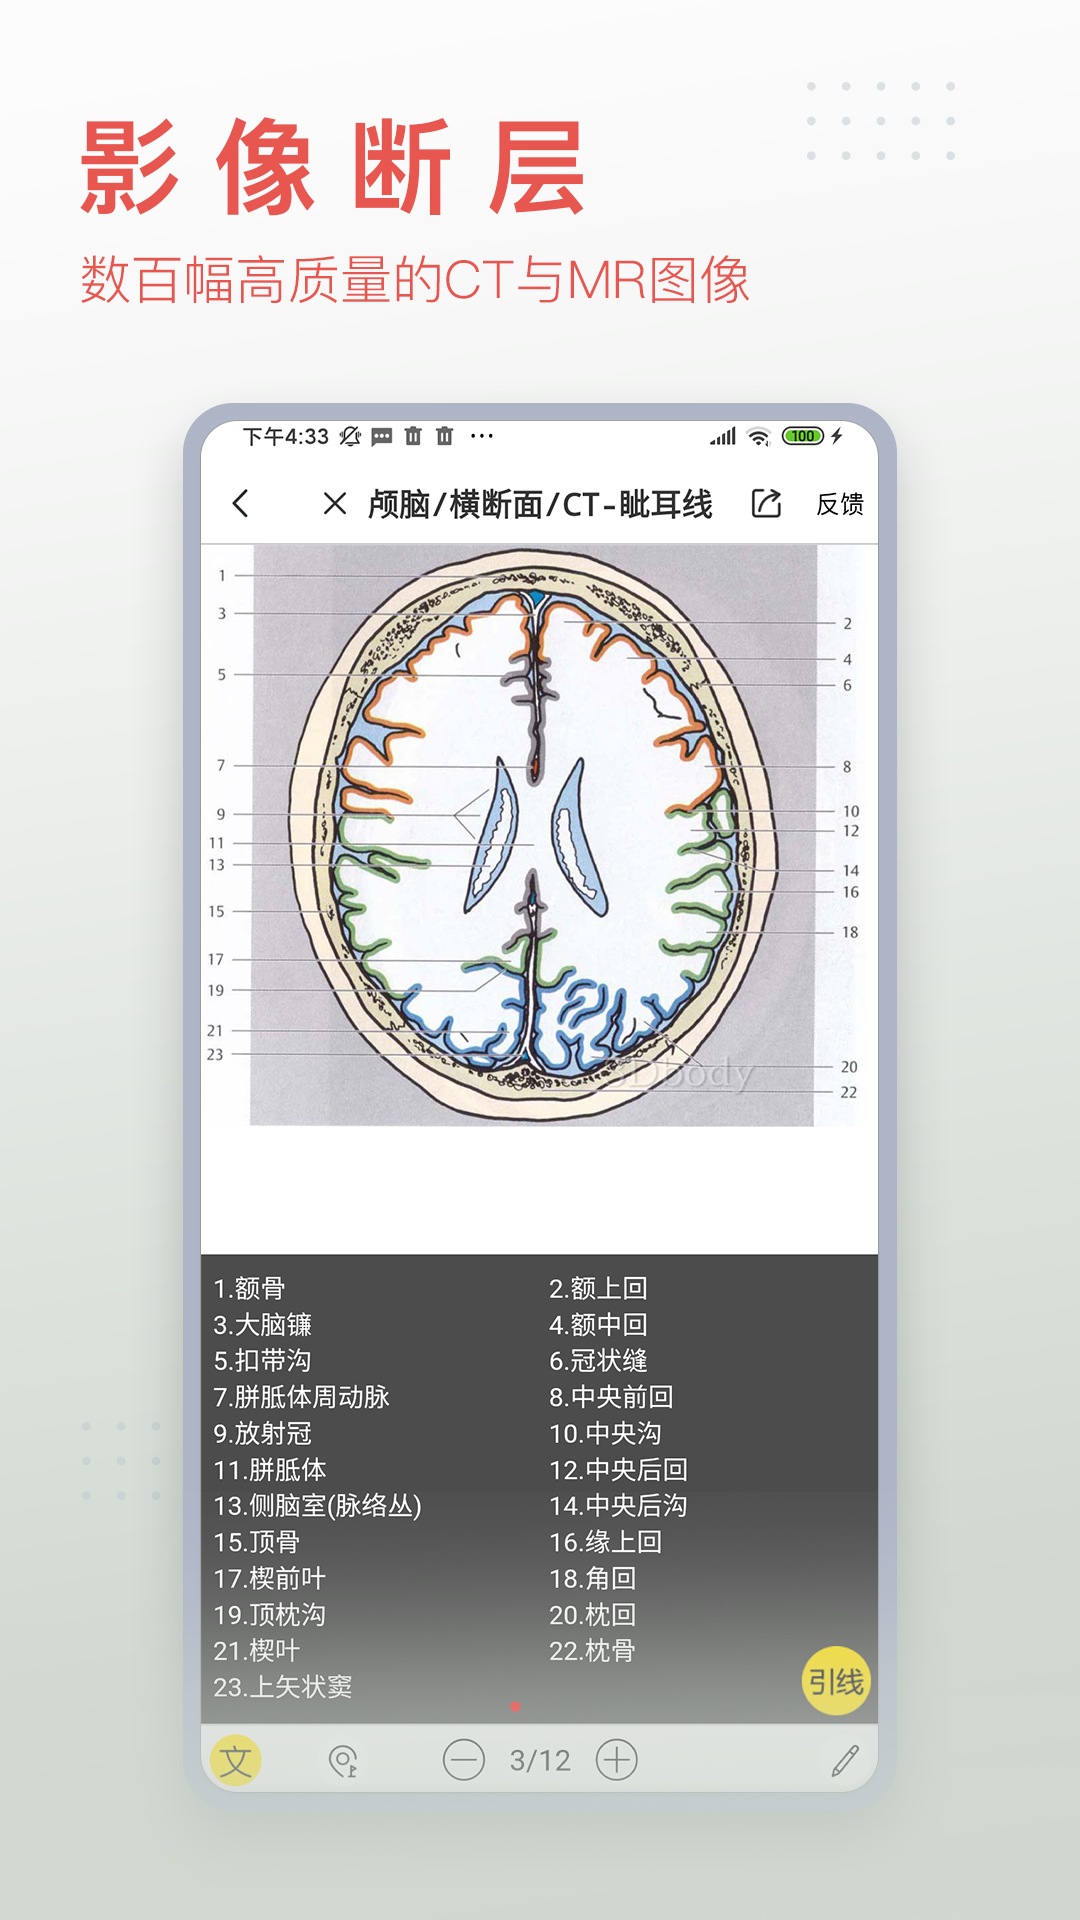

3dbody系统解剖手机版是专为医学行业打造的掌上人体解剖学习软件,详细的三维解刨图片,解释详尽。3DBody系统解剖手机版是系统模块,相较于局部模块版,解剖更加的详细,需要的赶紧下载吧。

3DBody作为集大成者,不仅数据详实,而且操作功能强大,国内外高度领先,通过本软件实时三维操作,轻易获得层层解剖人体的机会。作为内容最全面的3D解剖app,电脑版本已经被证实为最受欢迎的医学软件之一。

软件包括人体十二大系统的3D解剖.经络穴位和反射区,同时提供大量肌骨康复动画,全部三维体验,界面精美,内容专业,操作体验佳。

*断层影像